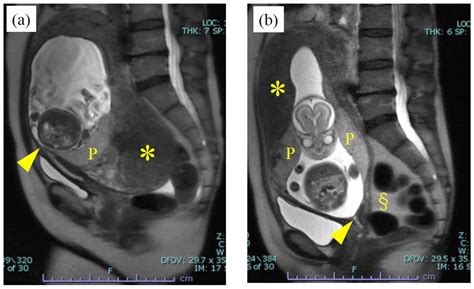

Ultrasound Imaging

Ultrasound imaging is a non-invasive technique that uses high-frequency sound waves to create images of the uterus and fetus. It is commonly used to:

• Confirm the presence of a gravid uterus

• Determine the gestational age of the fetus

• Assess fetal development and growth

• Identify any potential abnormalities or complications

Ultrasound examinations are typically performed at various stages of pregnancy to monitor the fetus's progress and detect any issues early.